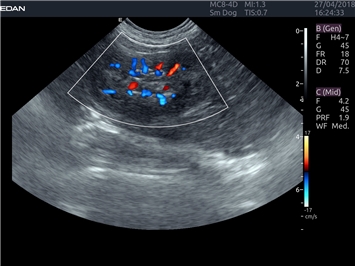

EDAN Acclarix LX4 VET

EDAN Acclarix LX4 VET представляет собой профессиональную ультразвуковую систему, специально разработанную для ветеринарных исследований. Сочетание стабильности, высокой производительности и эффективности делает эту систему идеальным выбором для современной ветеринарной практики.

Цветовой допплер:

Да

Трехмерная реконструкция ЦДК: